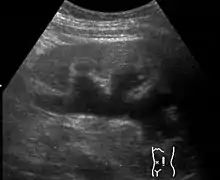

Наряду с пиелоэктазией почек врождённый гидронефроз часто обнаруживается при ультразвуковом обследовании плода[4] во время пренатальных скринингов. Во время беременности обычно обнаруживается гидронефроз лёгкой степени, в подобных случаях считается, что он обычно вызывается повышенной выработкой мочи у плода.. В большинстве случаев у грудных детей лечение может и не потребоваться[7].

Диагноз ставится на основании УЗИ, экскреторной урографии и ренографии.

При пренатальном диагностировании степень заболевания определяется размером почечной лоханки, замеряемым посредством УЗИ.